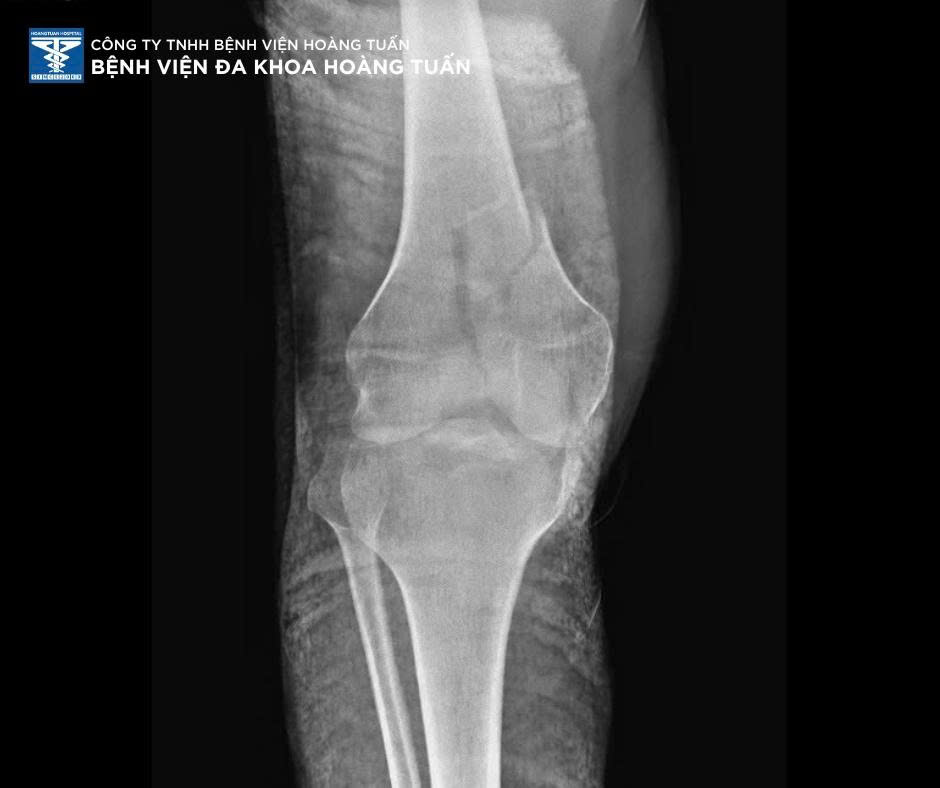

Sau khi thăm khám lâm sàng và thực hiện các cận lâm sàng cần thiết, BSCKI. Vũ Quốc Dũng – Khoa Ngoại CTCH Bệnh viện Đa khoa Hoàng Tuấn nhận định bệnh nhân chấn thương vùng đùi phải nghi do gãy đầu dưới xương đùi kèm tổn thương phần mềm – khớp gối, chỉ định nhập viện điều trị và can thiệp phẫu thuật kết hợp xương kịp thời nhằm phục hồi chức năng vận động, hạn chế các biến chứng lâu dài.